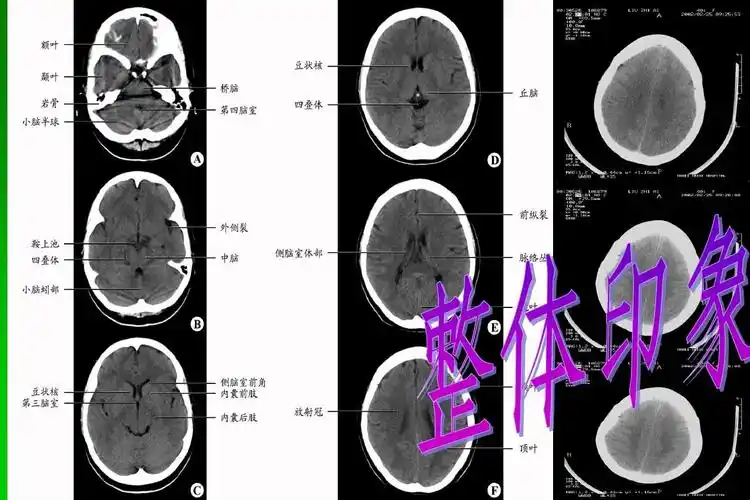

神经外科基础培训 头颅ct判读方法整体印象(中线结构,脑池,脑沟回